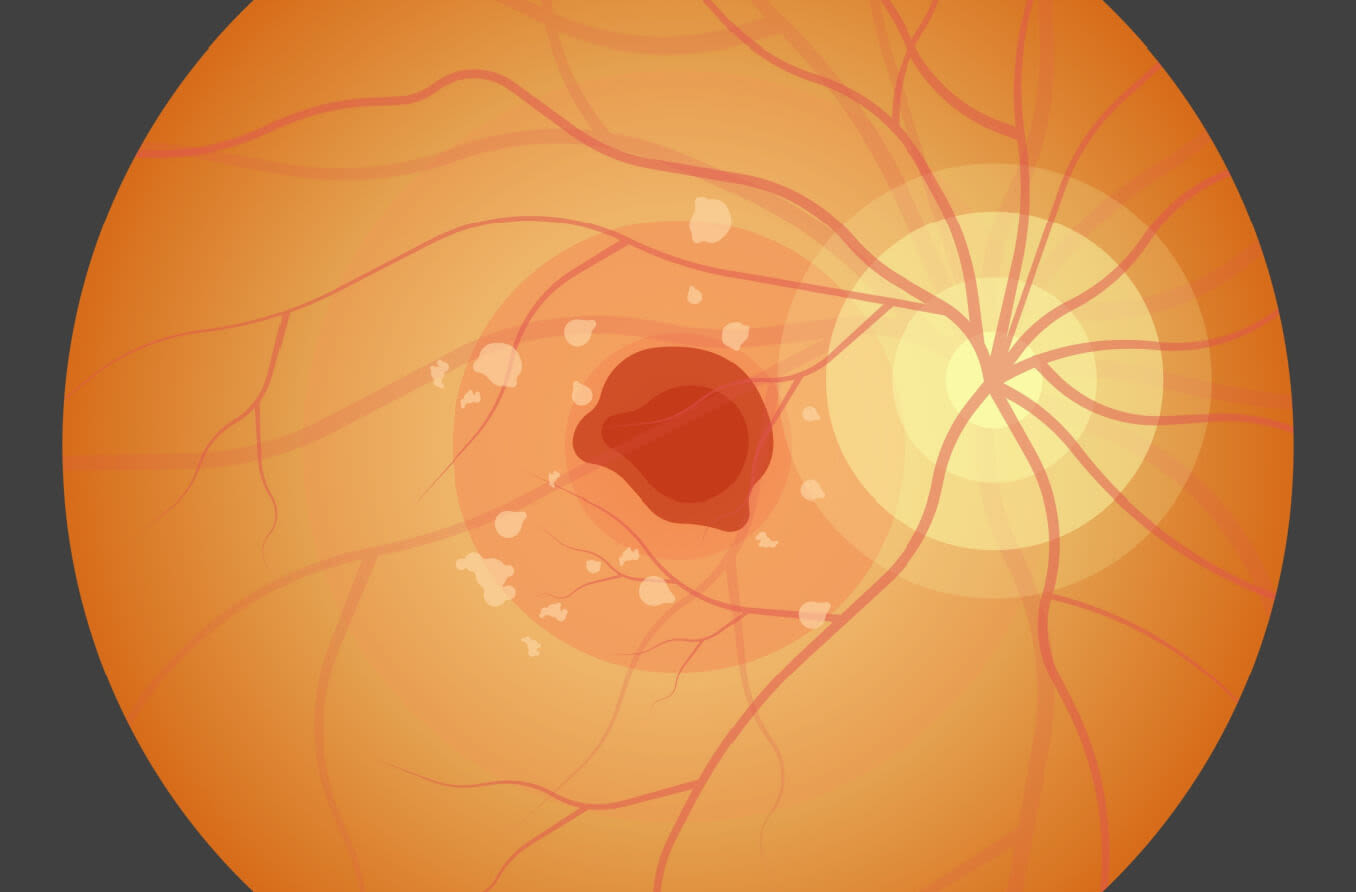

Morbus Stargardt bezieht sich allgemein auf eine Gruppe von Erbkrankheiten, die zu einer Veränderung der lichtempfindlichen Zellen im inneren Augenhintergrund (Netzhaut) führen, insbesondere im Bereich der Makula, wo die Feinfokussierung stattfindet. Es kommt zudem zu einem Verlust des zentralen Sehens, während das periphere Sehen in der Regel erhalten bleibt.

Morbus Stargardt wird anhand kleiner, gelbgefärbter Flecken aus Gewebeablagerungen (Drusen) diagnostiziert, die von der farbigen oder äußeren Abdeckung der Netzhaut (retinales Pigmentepithel) abgestoßen werden. Der fortschreitende Verlust der Sehkraft führt in den meisten Fällen schließlich zur Erblindung.

Symptome der Stargardt-Krankheit sind unter anderem verschwommenes oder verzerrtes Sehen, die Unfähigkeit, bei schlechten Lichtverhältnissen zu sehen und Schwierigkeiten, bekannte Gesichter zu erkennen. Im Spätstadium des Morbus Stargardt kann auch das Farbsehen verloren gehen.